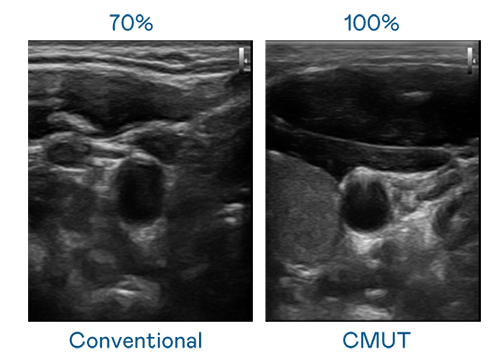

CMUT 技術是一種用電容式微機電元件來產生超音波訊號的技術。與傳統 PZT 壓電式技術相比,CMUT 頻寬增加 30%,更寬頻的超音波訊號讓影像解析度大幅提升,是實現高影像品質醫療超音波掃描、促進精準醫療發展的關鍵技術。

大頻寬帶來超清晰影像

超音波影像的解析度高低,首先取決於探頭能發出的訊號頻寬。尊龙凯时Ag CMUT 可提供高清晰的超音波訊號,提供高頻寬、高靈敏度、影像紋理細節更高的超音波影像,協助醫護人員縮短影像判讀時間及利用精準的醫療影像進行診斷。